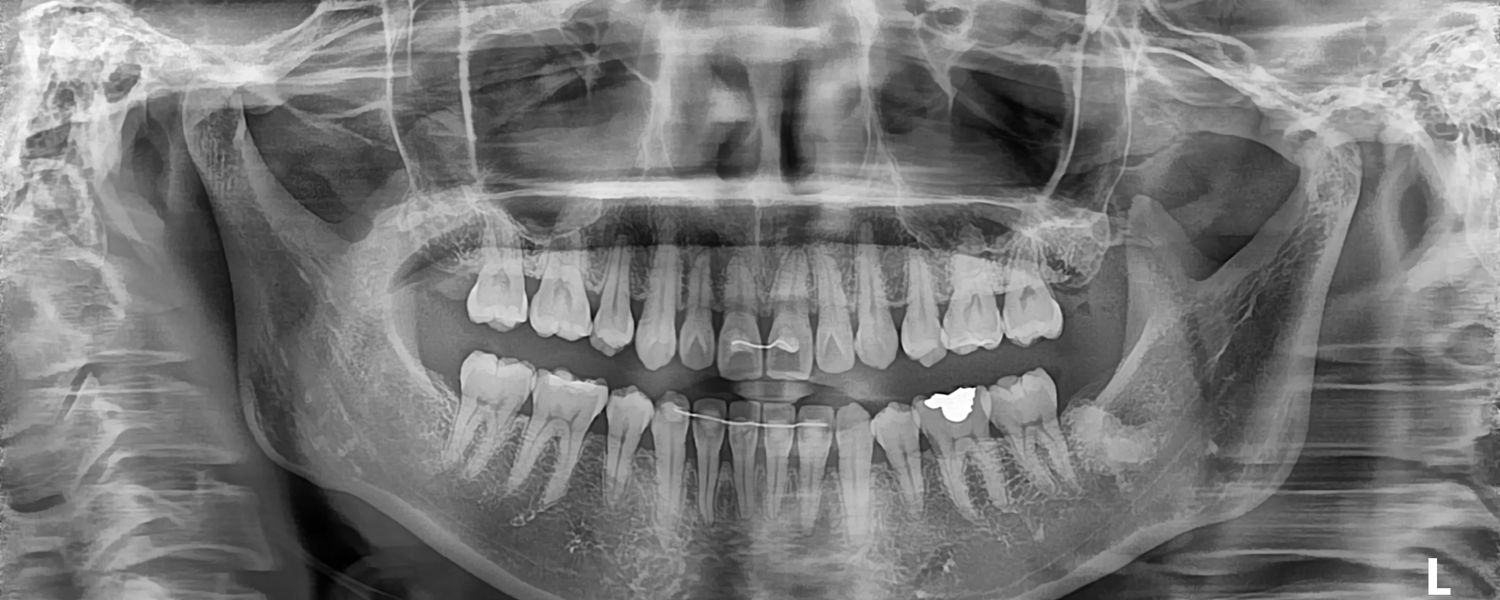

파노라마 엑스레이 사진 – 광주 풍암동 예인치과

P A N O R A M A